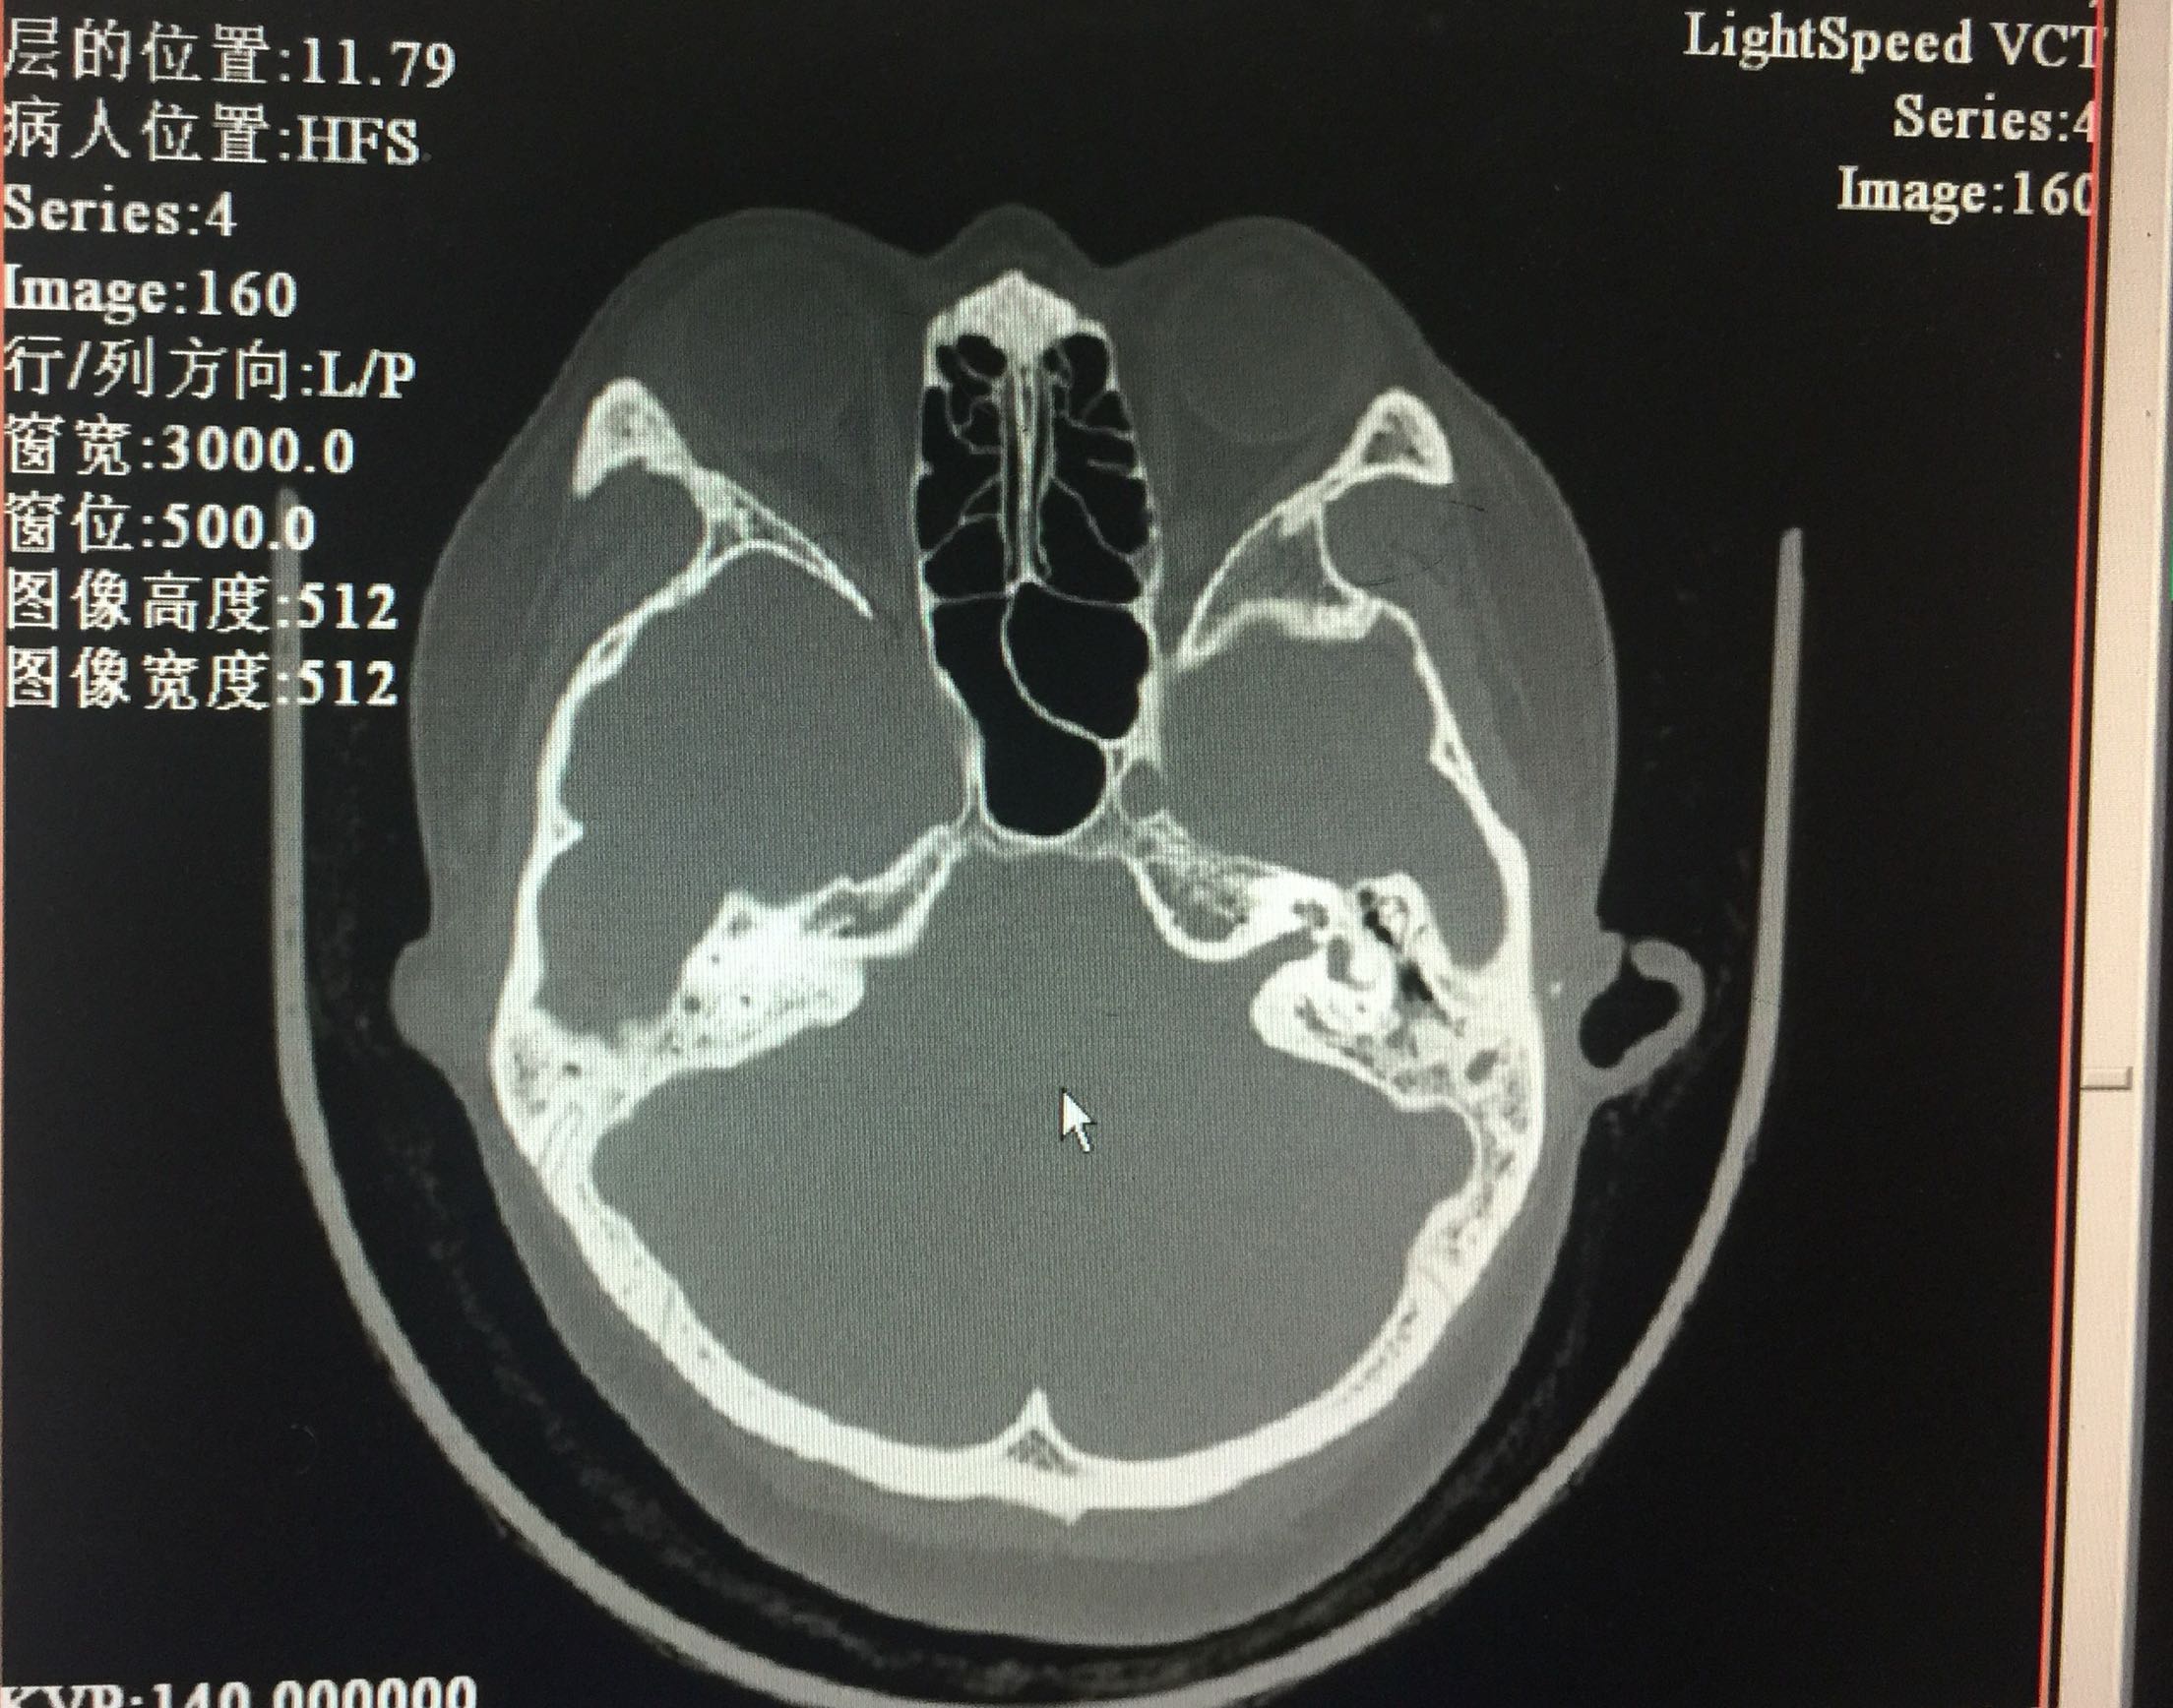

声导抗:双侧鼓室曲线B型,声反射未引出。颞骨CT:考虑双耳中耳乳突炎。

入院诊断:1.传导性聋(双)2.耳硬化症(双)?3.先天性小耳畸形(双)。治疗:入院后完善检查,全麻下行耳显微镜下左鼓室探查+骨岬开窗人工镫骨植入+外耳道成形术。左耳内切口,分离外耳道皮瓣见外耳道深部骨性狭窄,用电钻扩大外耳道,自后方完整掀开鼓膜后部。电钻磨开后鼓室,探查听骨链,见砧骨长突畸形变短,镫骨完全缺如,卵圆窗封闭,锤骨正常,锤砧关节活动好。用微钻圆窗后上相当于卵圆窗位置骨岬开窗,少量外淋巴液流出。选用合适人工听骨置于砧骨长脚上,末端植入骨岬开窗处。术后更正诊断为:1.传导性聋(双)2.先天性听骨链畸形(左)?3.先天性小耳畸形(双)。